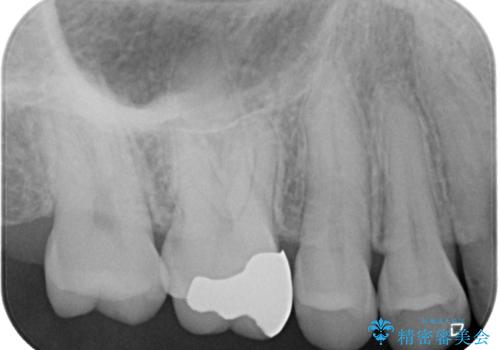

- 数年前他院にて治療した銀歯をやり替え希望の患者様です。

拡大鏡下で、銀歯、むし歯の除去を行い、セラミックインレーに適した形に整えました。